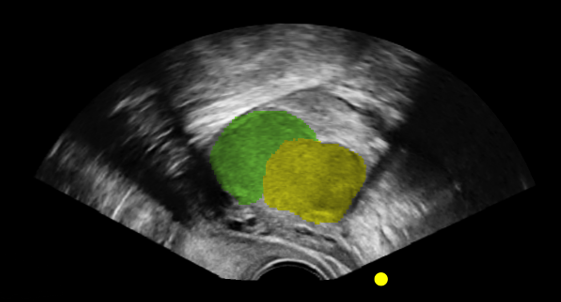

Our guided-learning replicates the experience of learning directly from a specialist. Available on each case*, the system provides highlighted ultrasound imagery with clear annotations, allowing learners to gain a clear understanding of what they are looking at, and what to look for in clinical practice – bridging the gap between theory and hands-on practice.

Dynamic highlighting and guided pathways encourage learners to progress at their own pace while reinforcing correct technique. This approach ensures that complex concepts – such as recognising anatomical variations or subtle signs of pathology – are made accessible, consistent, and clinically relevant. With our guided-learning, every scan becomes a repeatable opportunity to build skills under the guidance of an expert.

*Supplementary cases do not include highlighted anatomy